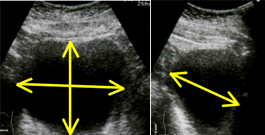

また前立腺のおおよその大きさ・形状と合わせて残尿をみるにはエコー検査が極めて有用です。尿を十分に溜めた状態で恥骨上にプローベを当てれば(高度の肥満症例でない限り)、前立腺の形状を概ね理解することができますし、時には膀胱内病変(腫瘍や結石)の診断にも有用です。また排尿後には残尿も測定可能でありこれにより大まかな排尿状態の理解が可能となります。前立腺体積、残容量ともに3方向を計測し0.55を乗ずることで回転楕円体に近似した体積が測定できます。薬剤治療にもかかわらず症状の改善されない方、あるいは前立腺体積が30ml以上、残尿が50ml以上が続くような場合は一度は泌尿器科の診察を受けられるのがよいかと存じます。体積の測定は3方向を測定し a x b x c x 0.55cm3 で計算する。(図の残尿であれば6.5 x 4.5 x 3.5 x 0.55=65.3ml)

残尿量の測定